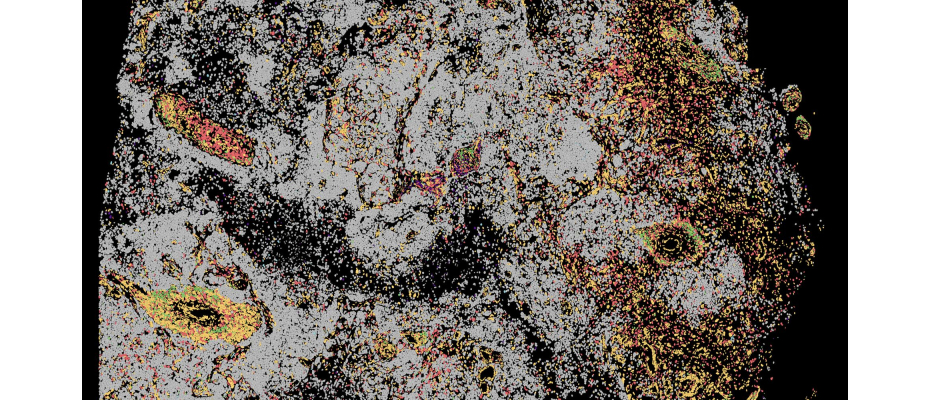

The researchers analysed over 70,000 cells from patients with cerebrospinal fluid lymphomas, glioblastomas, or brain metastases from melanoma, breast, and lung cancer, comparing them with cells from patients with neuroinflammatory disorders. CNAG’s team used pioneering sequencing techniques that allowed the RNA of each cerebrospinal fluid cell to be studied individually, revealing how genes are activated and how cells respond to the tumour, including T-cell receptors, which act as “sensors” to detect and attack cancer, with their expansion reflecting the strength of the immune response. The analysis was complemented with tumour DNA to identify potential vulnerabilities and spatial transcriptomics to produce a detailed map of cells in their environment.